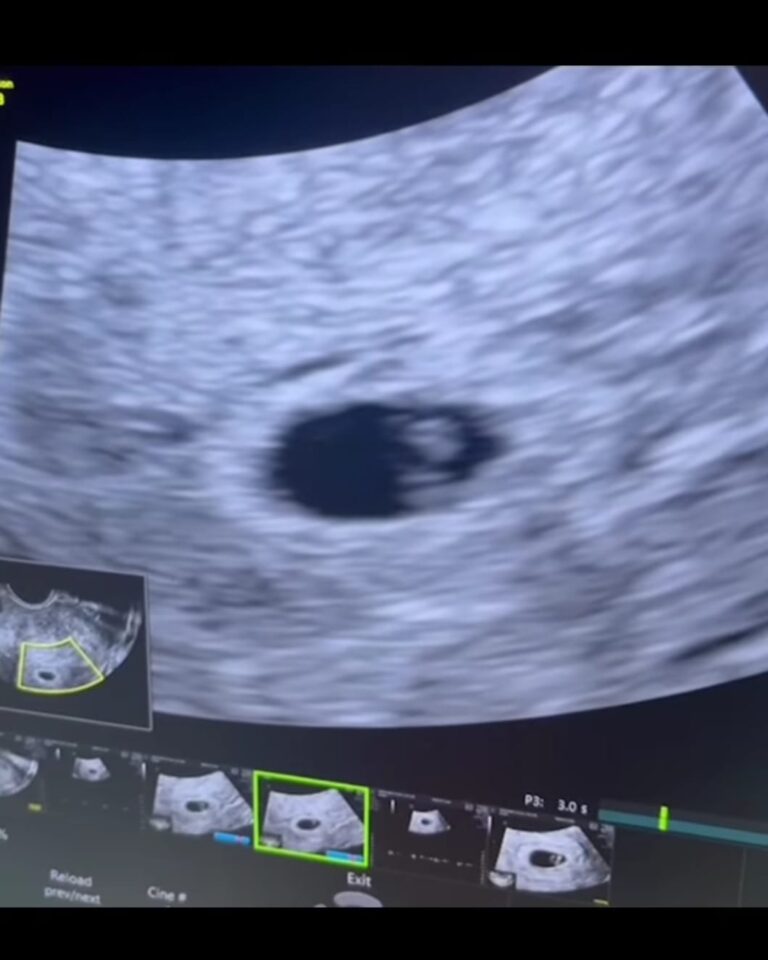

โดยยุ้ย จีรนันท์ ได้โพสต์ภาพพร้อมระบุข้อความว่า “เธอ+ฉัน = เรา 3 คน ทุกปาฏิหาริย์ต้องใช้เวลา…เบบี๋น้อยของเรามาแล้วน๊าาา ดีใจที่สุด… มีความสุขที่สุดเลย”

ส่วนทางด้านธัญญ์ ธนากร ก็ได้โพสต์ภาพด้วยเช่นกัน พร้อมระบุข้อความว่า “วันนี้ที่รอคอยเติมเต็มครอบครัวของเราหนูจะเป็นดวงใจของพ่อกับแม่นะ”